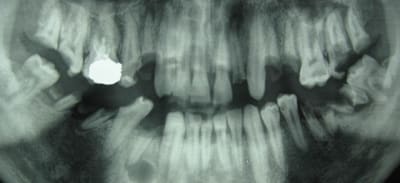

voici un jeune patient vu en urgence, le radiologue du coin fait la pano ds l'urgence aussi

antibio avant de preparer les alvulsions.....

jamais revenu

le france est un pays developpé ou il a tjrs vecu (vive le fluor!!)

même le traitement radiculaire sur 16 est abimé pffff!